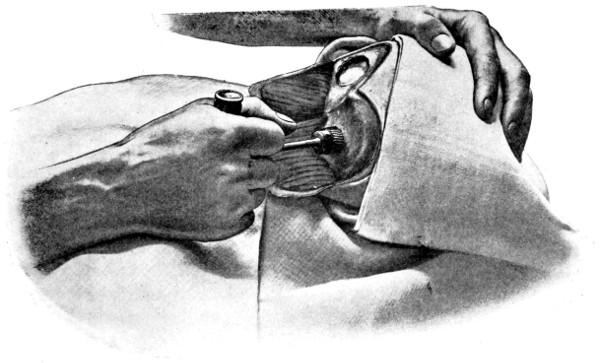

Fig. 18. Second Stage in the Formation of an Osteoplastic Flap. The bone-flap turned down and the dura mater exposed.